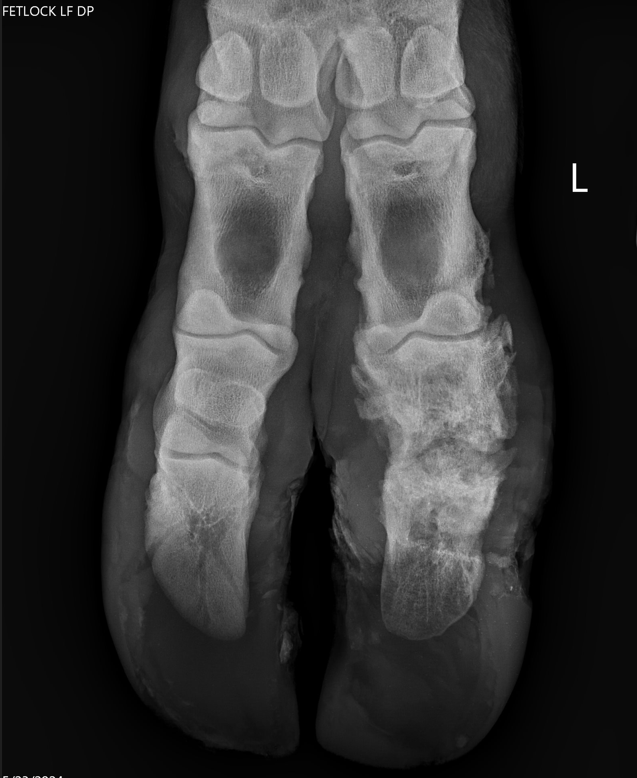

Veterinary radiography (also known as x-rays) provides an in-depth, noninvasive way to image the bones and internal organs of animals. These radiographs help veterinarians diagnose and monitor various conditions, such as bone fractures, dental issues, and internal organ problems.

The process involves positioning the animal and capturing images that can reveal abnormalities

and guide treatment decisions. Veterinary radiography is a critical tool for providing accurate and effective care to animals.